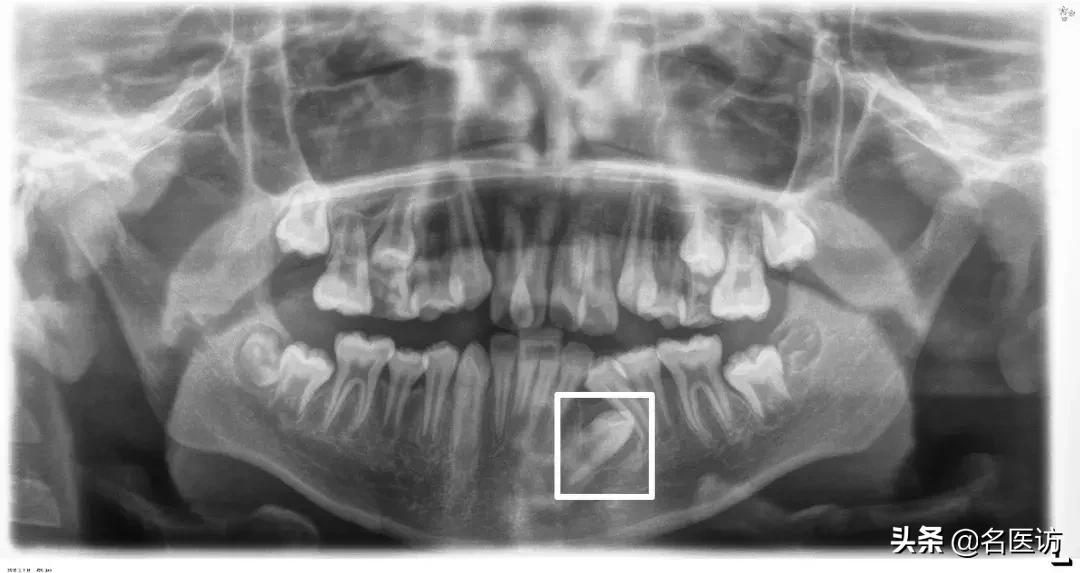

3、颞下颌关节

髁突磨损

全景片观察的主要是颞下颌关节的对称性和髁突的形态,如果关节严重不对称或髁突有明显磨损,需要去做进一步的详细检查,不能贸然开始做矫正。